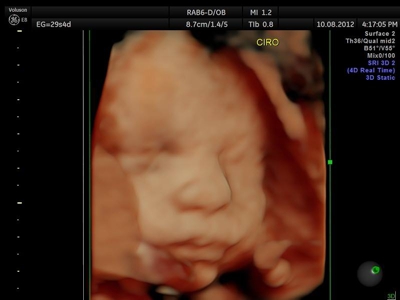

Si bien la Ecografía 4D HD/5D puede realizarse en cualquier etapa del embarazo, recomendamos realizarla entre las semanas 24 a 32 de gestación ya que se pueden observar rasgos bien definidos en el bebe.

Fotografías de ecografías 4D HD/5D

Haga click sobre las imágenes para ampliar